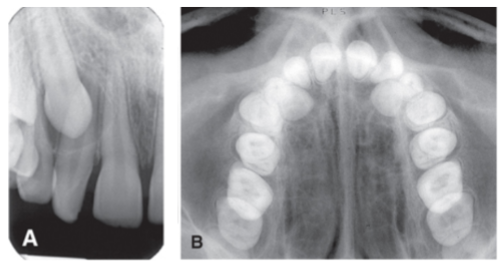

Projections show the entire length of tooth and surrounding peri-radicular bone

PA

Projections show only the crowns of teeth and adjacent alveolar crests

BTW

Projections show an area of teeth and bone larger than periapical images

Occlusal

Primary objectives of periapical projections

Capture full length of root and 2-3mm of periapical bone, entire crowns and open contacts, and capture all interproximal bone levels

Occlusal images are used where

Pediatrics for evaluation of developing dentition